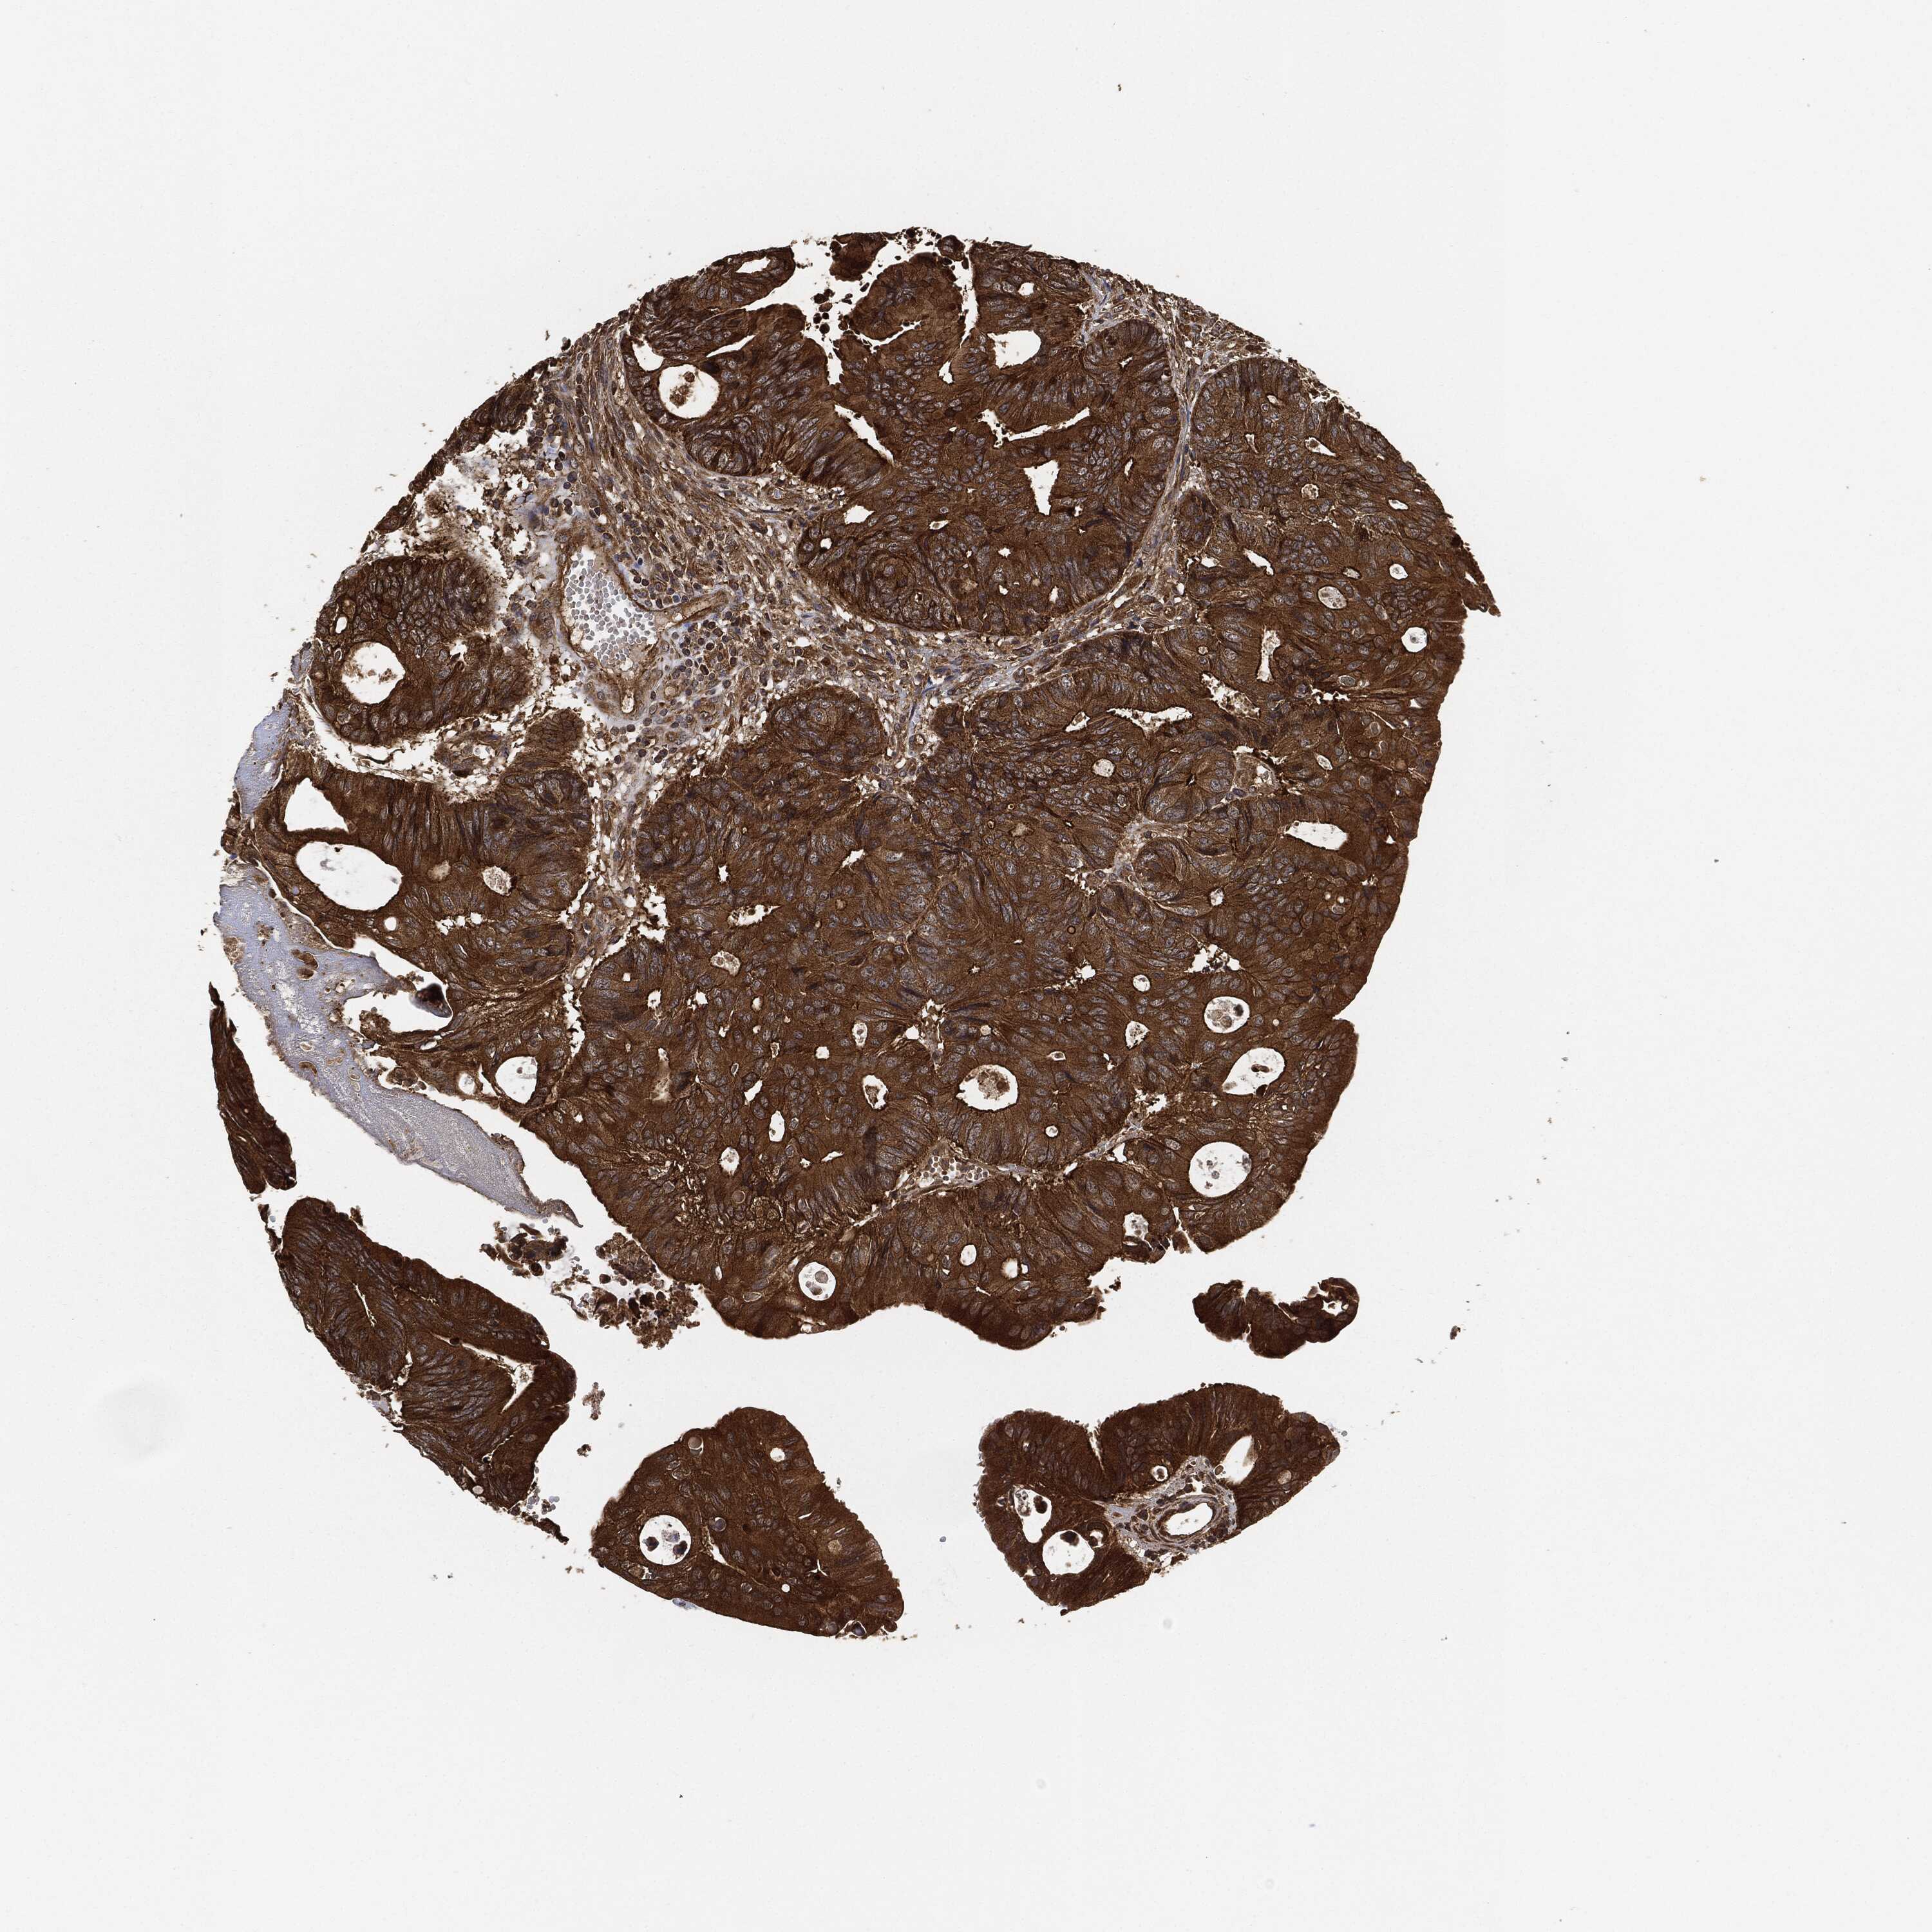

CANCER COLORECTAL CANCER Show tissue menu

Colorectal cancer

Human cancer

Colon adenocarcinoma